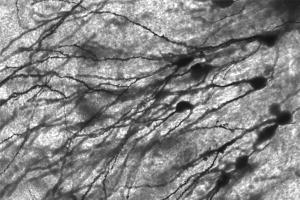

צילום מיקרוסקופי של תאי מוח – נשטפים בקלות בזמן שינה. Wikimedia/ MethoxyRoxy